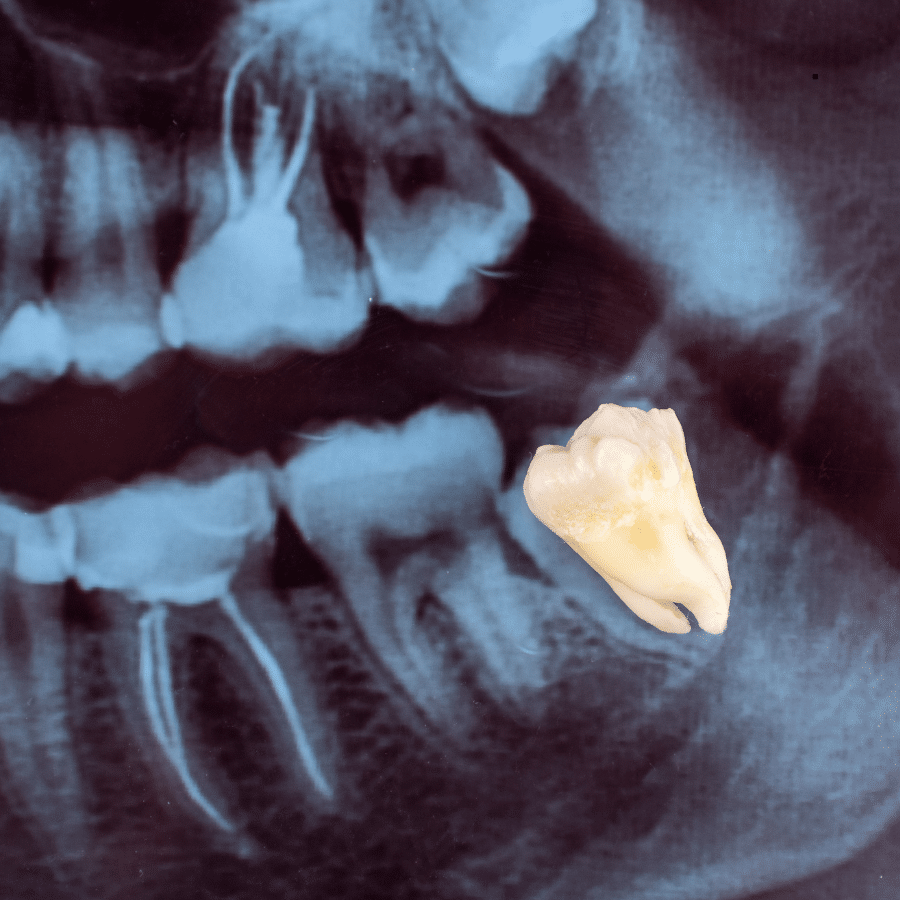

Las extracciones es uno de los procedimientos más agresivos ya que consiste en quitar una o varias piezas de la boca. Una extracción se debería realizar solo en casos en los cuales otros tratamientos para salvar la pieza se hayan evaluado y considerado no adecuados. Las causas más comunes para la extracción dentaria simple son la caries dental y la enfermedad periodontal, asociadas o no a dolor e infecciones repetitivas. Otras causas posibles son: dientes supernumerarios, dientes en áreas sometidas a irradiación, causas protésicas y ortodóncicas.

En La Clínica Dental El Bosque recomendamos la extracción de cordales cuando éstos dañan o afectan a los otros dientes o bien causando caries o al desarrollarse, ya sea porque los empujan o porque salen torcidas o parcialmente. En el caso de que se encuentren incluidas (es decir, que se sitúen bajo la encía y no salgan), también se aconseja su extracción, dado que pueden causar no solo problemas como apiñamiento dental, sino quistes o infecciones.

Hay dos tipos de extracciones; simples y de cordales.